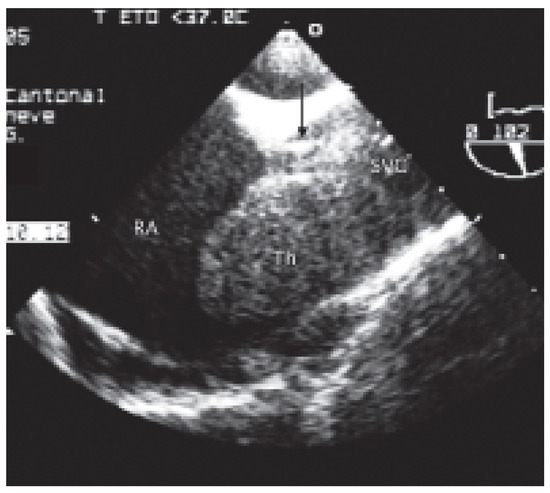

Case report